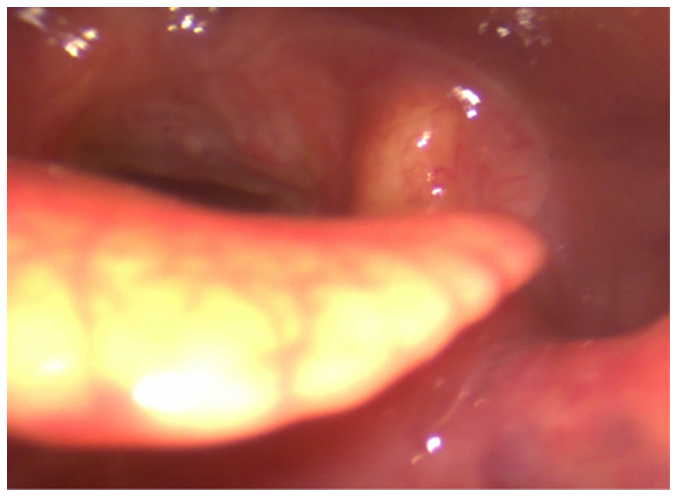

The ENT performed videoendoscopy with 0° rigid and flexible optic fibers. The findings from the videoendoscopy revealed significant abnormalities at the inner third of nasal fossae, pharynx, left tonsillar pillar, left part of soft palate, uvula, (Figure 1) epiglottis (Figure 2) but still sparing glottal and tracheal regions.

Figure 1 Mycosis involving istmus fauci, from left amygdala till soft palate and uvula.